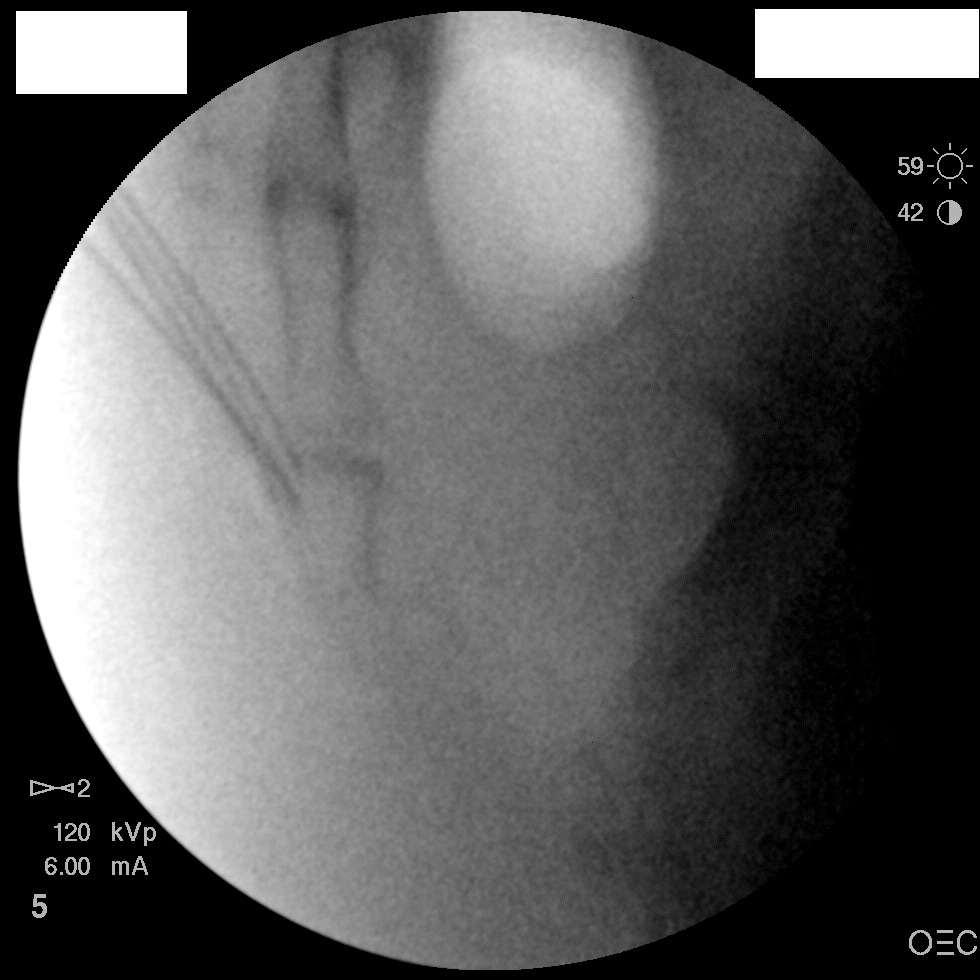

I have a patient with several months of coccyx pain. Worse with sitting, TTP over coccyx. Otherwise normal exam. No trauma, but she has an anteriorly displaced coccyx. Failed NSAIDs and no one around me does good pelvic floor PT. I scheduled her for ganglion impar injection, but her insurance won't pay for it. They wouldn't even let me to a peer-to-peer... they just straight up said they won't cover it. Any other treatment options? I don't want to send her to a surgeon. Thanks.